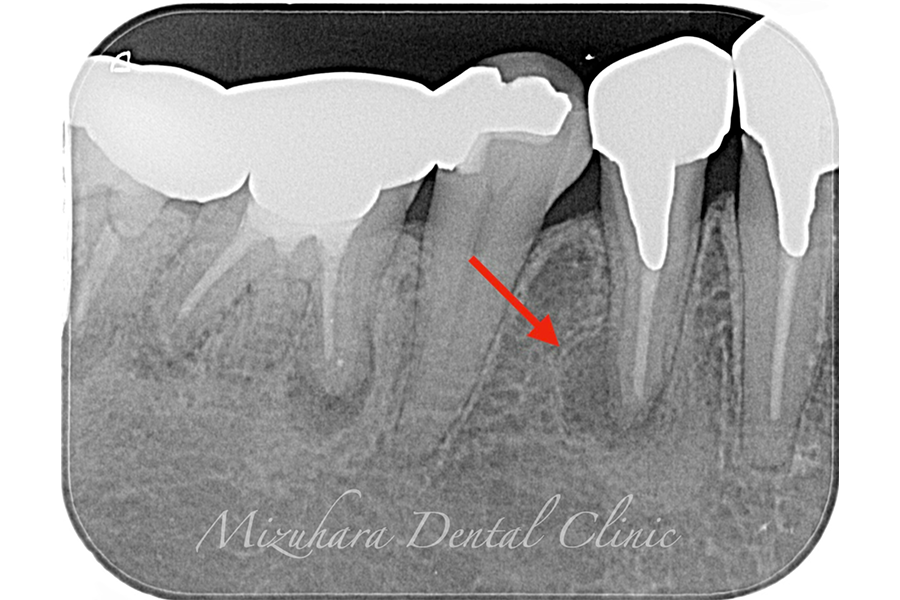

予知性の高い治療を提供できるだけ患者様の大切な歯を残し、10年、20年先まで健康な状態を保てるよう、長期的な視点で治療を計画します。そのために最も重要なのが、「診査」と「診断」です。的確な診断は精密な診査から生まれ、治療結果を大きく左右します。問診や簡易検査だけでは見逃されがちな病変も、CTやマイクロスコープなどの最新の医療機器を活用し、時間をかけて丁寧に「診査・診断」を行います。

世界基準の成功率を目指した精密根管治療

当院では豊マイクロスコープ、ラバーダムを使用し、世界基準の成功率を目指した精密根管治療による「歯を残す」ための治療をご提供します。